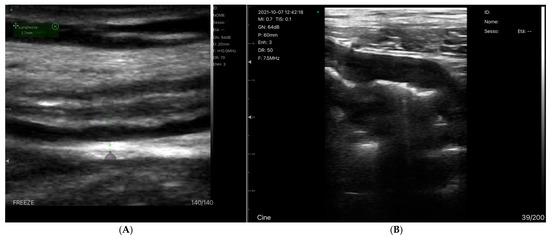

Assessing Venous Congestion in Acute and Chronic Heart Failure: A Review of Splanchnic, Cardiac and Pulmonary Ultrasound: Part 1: Conventional B-Mode, Colordoppler, and Vexus Protocol

by Francesco Giangregorio, Ester Centenara, Samanta Mazzocchi, Luigi Gerra, Francesco Tursi, Davide Imberti and Daniela Aschieri

Background/Objectives: Heart failure (HF) causes systemic and regional haemodynamic alterations that extend beyond the heart, profoundly affecting splanchnic circulation. Venous congestion is a hallmark of heart failure (HF) and a major determinant of clinical deterioration and multiorgan dysfunction. The splanchnic venous system—comprising the portal, hepatic, and renal veins—acts as a key reservoir for intravascular volume redistribution. Conventional ultrasound (US), using grayscale and Doppler imaging, offers a direct, non-invasive approach to visualize these haemodynamic changes. This review, Part 1 of a two-part series, summarizes the current evidence and clinical applications of conventional US for assessing splanchnic, cardiac and pulmonary vascular alterations in patients with HF. Methods: A systematic review was performed in PubMed, Embase, and the Cochrane Library up to current date, following PRISMA 2020 guidelines. Eligible studies included adult human investigations evaluating splanchnic vascular changes in HF using B-mode, color Doppler, or pulsed Doppler ultrasonography. Exclusion criteria were pediatric, animal, or non-English studies and non-standard imaging methods. Data on ultrasonographic parameters, haemodynamic correlations, and prognostic value were extracted and qualitatively synthesized; Results: A total of 148 eligible studies (n ≈ 7000 patients) demonstrated consistent associations between HF severity and alterations in splanchnic, cardiac and pulmonary flow. Findings included increased bowel wall thickness, portal vein dilation with elevated pulsatility, and monophasic or reversed hepatic vein waveforms, all correlating with higher right atrial pressure and adverse clinical outcomes. The integration of these parameters into the Venous Excess Ultrasound (VExUS) framework enhanced detection of systemic venous congestion, in addition to the study of the cardiac and pulmonary circulation. Conclusions: Conventional ultrasound assessment of splanchnic vasculature provides valuable, reproducible insight into systemic congestion in HF. Incorporating hepatic and portal Doppler indices into standard evaluation protocols may improve risk stratification, optimize decongestion therapy, and guide management. Further prospective randomized and outcome-driven studies are required before VExUS-based therapeutic thresholds can be universally recommended and define prognostic thresholds. Full article

(This article belongs to the Special Issue Multiparametric Ultrasound Techniques for Liver Disease Assessments)